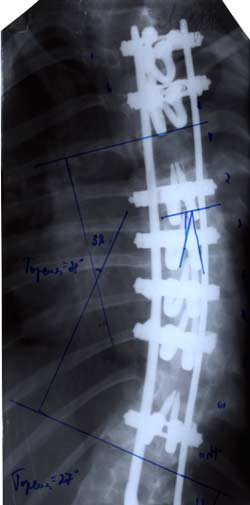

История создания устройства для

оперативного лечения сколиотической

деформации началась в 70-е годы. А.А.

Гайдуков и Л.Л. Роднянский предложили

динамическую конструкцию эндокорректора.

Она представляла собой пластины уложенные

вдоль позвоночника на вершине деформации

и фиксированные проволокой к дужкам

или остистым отросткам позвонков на

нескольких уровнях. Но данная конструкция

не оправдала надежд авторов и была

оставлена.

|

В дальнейшем

А.А. Гайдуков разработал и создал

эндокорректор с деротационными скобами

с фиксацией в блоках креплений на

нескольких уровнях. Данный эндокорректор

позволил эффективно на 60-100% корригировать

деформацию при сколиозе III-IV степени.

Но тяжелая многочасовая операция,

травматичность вмешательства, проволочная

фиксация и нередкие неврологические

осложнения ограничивали применение

данной методики.

Л.Л.

Роднянский предложил для коррекции

сколиотической деформации одно-пластинчатый

эндокорректор. Методику характеризовала

малая травматичность и безопасность

оперативного вмешательства. Однако,

недостаточная жесткость конструкции,

малое число блоков крепления корректора

не позволяли оперировать тяжелые формы

деформации. В случаях вмешательства у

пациентов с начальной стадией заболевания,

с деформацией I-II степени не удавалось

избежать прогрессирования искривления.

В послеоперационном периоде происходила

достаточно быстрая потеря коррекции и

в общем она составляла приблизительно

40%. Кроме этого достоверно нарастала

ротационная деформация позвоночника

на вершине искривления.

Начиная с

80-х годов, благодаря тесному многолетнему

сотрудничеству инженеров отдела

медицинской техники ГП КРАСМАШ завода,

научно-производственного центра МЕДИЛАР,

Института Восстановительной медицины

и кафедры травматологии и ортопедии

Красноярской Государственной медицинской

Академии была внедрена новая конструкция,

которая принципиально отличается от

всех предыдущих, но, в тоже время,

сохранила их главное рациональное

зерно.